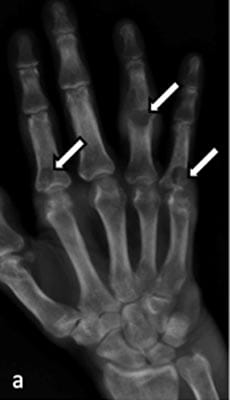

Crystal deposition diseases are a spectrum of arthritides induced by cellular reaction and inflammatory response in and around joints due to microcrystals. The most common of these disorders are gout, calcium pyrophosphate dihydrate and calcium hydroxyapatite deposition disease. The difference in the pathophysiology of these diseases means they are unique in their clinical presentation and radiological appearances. Imaging plays a pivotal role in the diagnosis and subsequent monitoring of treatment response and is a cornerstone of management. Conventional radiography remains the primary modality, but there is an increasing role of ultrasound, CT, MRI and dual energy CT.